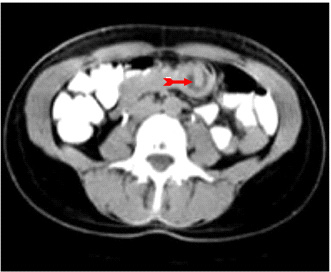

לעתים רחוקות, כדי לקבוע את גובה החסימה ואת מידתה בחולים הלוקים בחסימה דינמית, או כדי להבדיל בין שתי צורות החסימה, יש לצלם את החולה לאחר בליעת חומר ניגוד נספג מסוג גסטרוגרפין. בחסימה דינמית ניתן למצוא התקדמות של חומר הניגוד עד לחסימה (תצלום 6.4), ואילו בחסימה אדינמית ניתן למצוא אמנם מעבר לכל אורך המעי, אך מעבר איטי ביותר. לחולים שבהם יש חשד לחסימת הכרכשת, אין לתת בריום דרך הפה אלא לבצע חוקן בריום תחילה. ב- CT בטן עם חומר ניגוד ניתן לראות לולאות מורחבות שלאחריהן לולאות התמט, בצקת של הלולאות ונוזל ביניהם (תצלום 7.4).